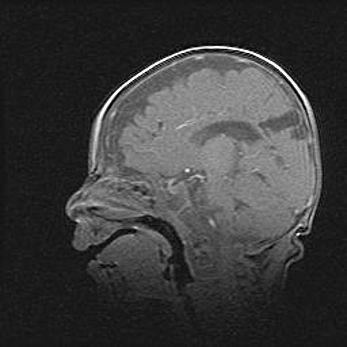

Открытая гидроцефалия.

Возраст: 9 месяцев 12 дней

Вес: 6800 г

Пол: мужской

Окружность головы: 41,5 см

Срок гестации: 28 недель

Гидроцефалия головного мозга у новорожденных имеет характерный признак: опережающий рост окружности головы приводит к визуально хорошо определяемой гидроцефальной форме сильно увеличенного в объёме черепа. Детские неврологи определяют следующие симптомы гидроцефалии у грудничков: выбухающий напряжённый родничок, частое запрокидывание головы, смещение глазных яблок к низу.